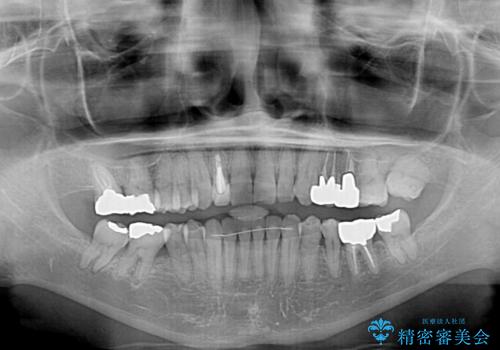

- 前歯のクロスバイトを気にして来院された患者様です。

骨格的に下顎が前方位ではありますが、歯並びが改善されれば正常咬合となることが分かったため、インビザラインを用いて咬み合わせを改善していくこととしました。

インビザラインは四六時中上下のマウスピースを介した咬合状態となるため、治療過程にて奥歯が接触しないという状態が続くことがあります。

奥歯の非接触は機能面において大きな障害であるため、この問題を解決しない限り矯正治療を終えることはできません。

インビザラインでの矯正治療が長期化してしまう要因の1つです。